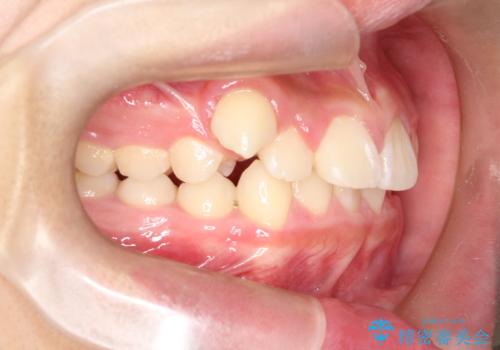

八重歯・歯並びのデコボコとディープバイトを改善した抜歯ワイヤー矯正症例

- 八重歯と咬み合わせを治したいを主訴にご来院された患者様です。

矯正の精密検査の結果上顎左右4番の計2本を抜歯し、審美性に配慮したワイヤー矯正装置(審美装置)を用いて治療を行いました。